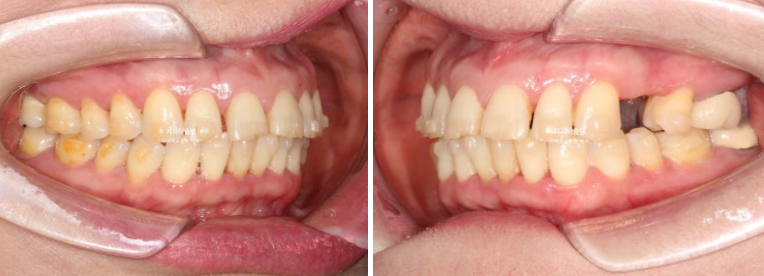

첫세트 장치 14개를 다 낀 후 모습입니다.

25년 1월 장치를 낀지 4개월 후 모습입니다.

앞니 사이 틈은 상당히 줄었고

임플란트 할 공간도 적절히 조절합니다.

미진한 부분을 더 개선하고자 추가장치 제작에 들어갑니다.

추가장치는 이래 저래 환자분 사정으로 인해 꾸준히 열심히 끼지는 못 했습니다.

그래서 추가장치를 쉬엄쉬엄 거의 1년간 꼈습니다.

26년 1월 마지막 장치를 다 끼고 남은 공간을 레진으로 메꾸기로 합니다.